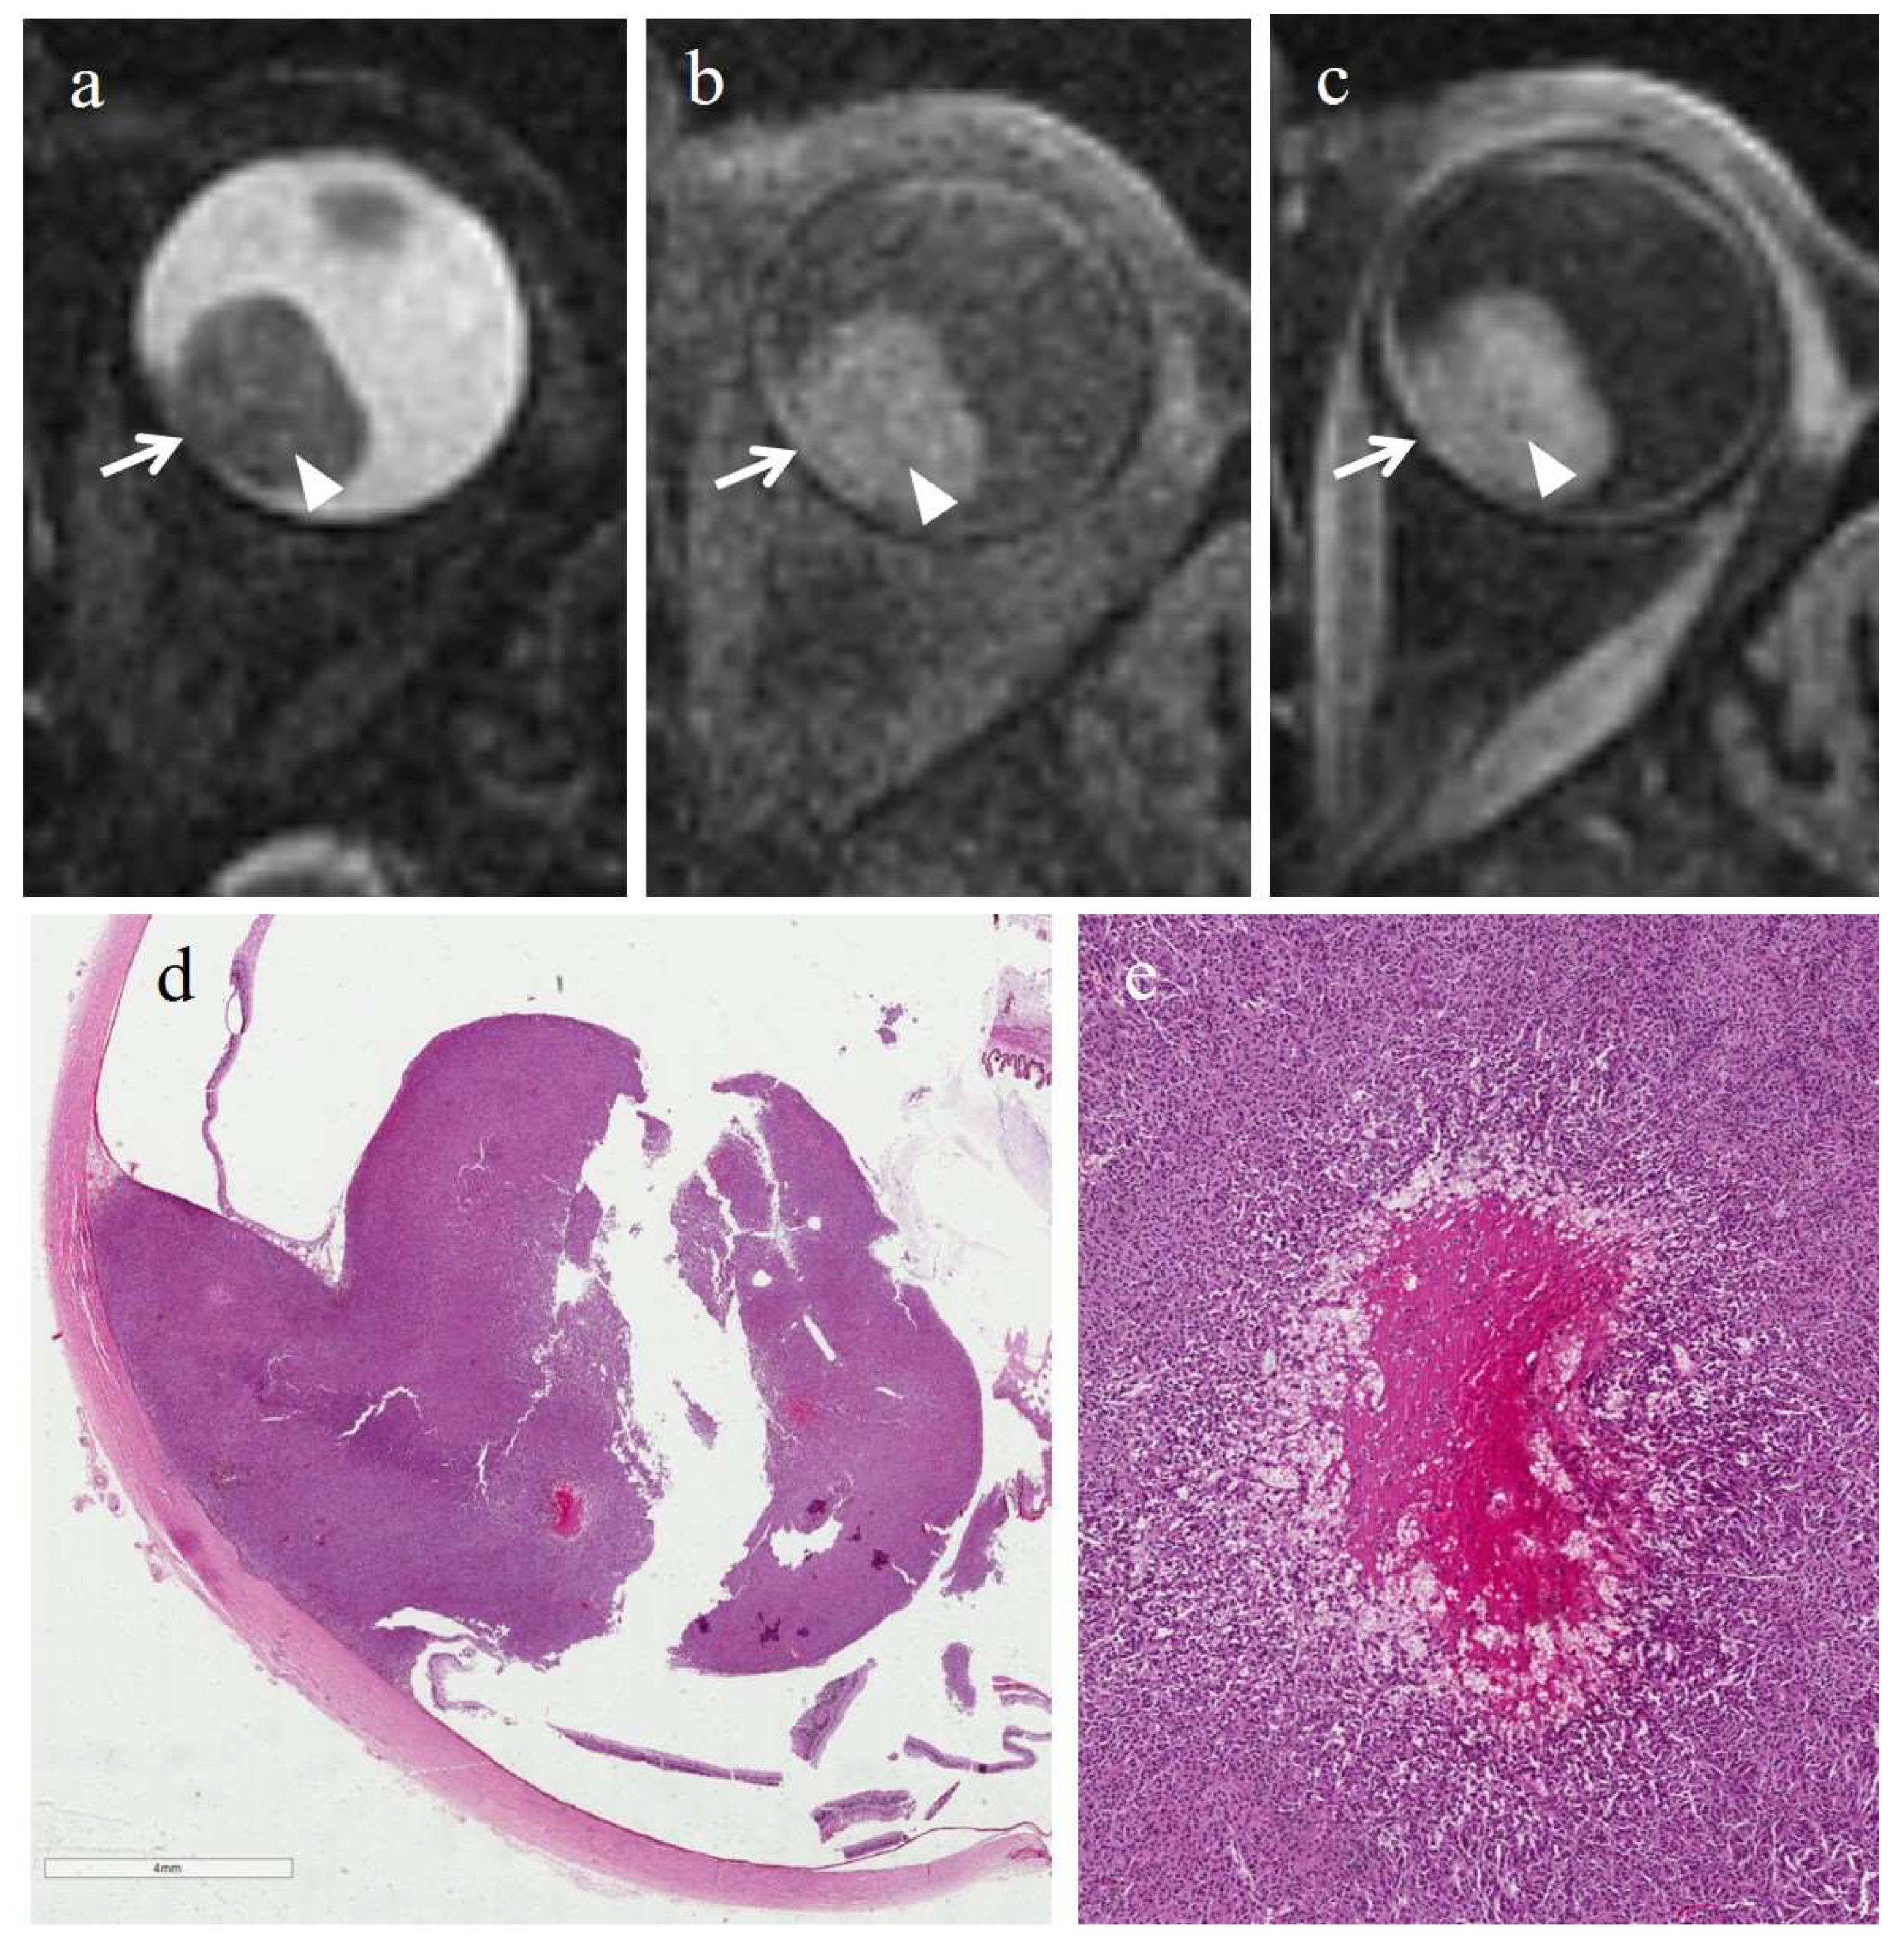

| Patient | Histologic Type | Degree of Pigmentation | Degree of Necrosis | Necrotic Pattern |

|---|---|---|---|---|

| 1 | Epithelioid cell | Pigmented | Grade I | Multiple foci- hemorrhagic/coagulative-type, tumor necrosis |

| 2 | Epithelioid cell | Poorly pigmented | Grade I | Multiple foci- hemorrhagic/coagulative-type, tumor necrosis |

| 3 | Spindle cell | Pigmented | Grade II | Multiple foci tumor necrosis |

| 4 | Mixed cell type | Pigmented | Grade I | Multiple foci tumor necrosis |

| 5 | Spindle cell | Pigmented | Grade I | Multiple foci- hemorrhagic/coagulative-type, tumor necrosis |

| 6 | Mixed cell type | Poorly pigmented | Grade I | Multiple foci- hemorrhagic/coagulative-type |

| Patient | T2 | T1 | Gd-T1 | DWI | ADC × 10−3 mm2/s ** |

|---|---|---|---|---|---|

| 1 | - | - | - | - | 1.04 |

| 2 | - | - | - | - | 1.22 |

| 3 | - | - | - | - | 0.63 |

| 4 | - | - | - | - | 0.78 |

| 5 | - | - | - | - | 1.05 |

| 6 | Hyperintense | Hypointense | No enhancement | No restriction | 0.80 |